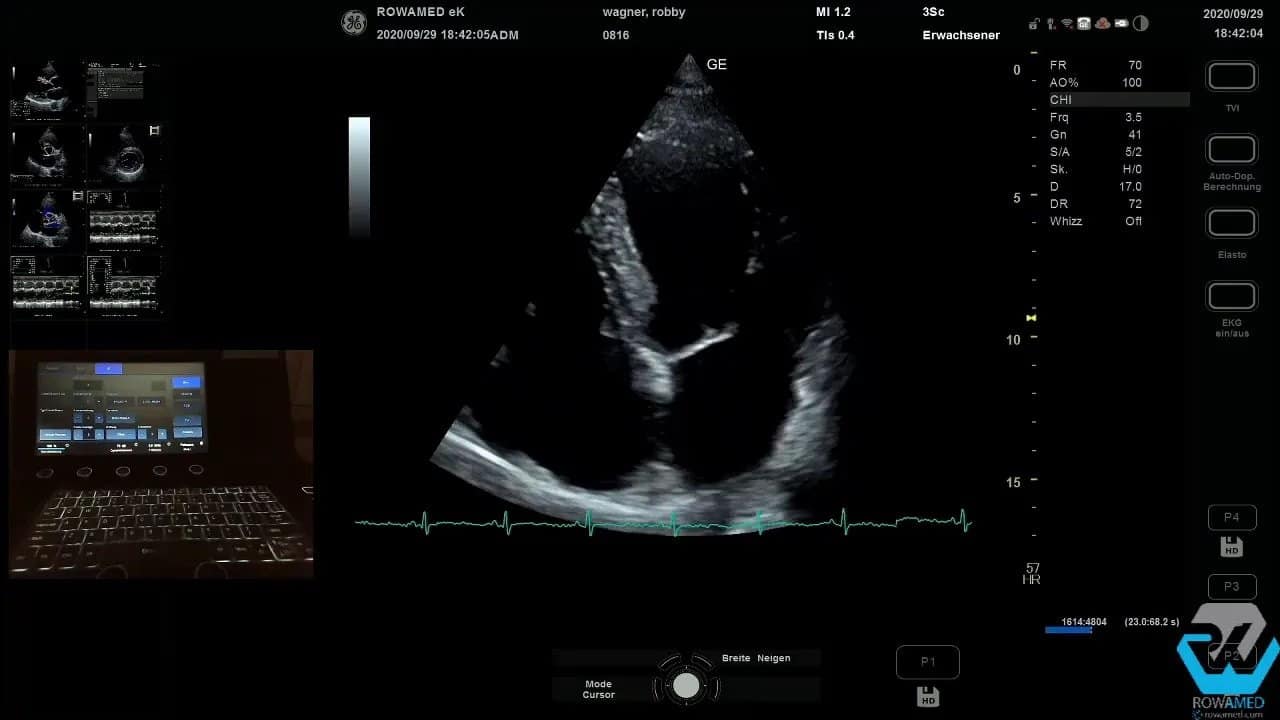

Step 7: Den apikalen Vierkammerblick optimieren

Nach Abschluss der parasternalen Ebenen folgt die apikale Anlotung. Häufig braucht es dafür nur eine kleine Lagerungskorrektur. Der Patient rutscht etwas nach vorne, der Schallkopf kommt besser unter den Thoraxrand, und plötzlich wird aus einem mittelmäßigen ein sehr guter Vierkammerblick.

Wenn das Bild grobkörnig wirkt, können Sie mit Bildglättung oder Frame Average arbeiten. Dadurch wirkt die Darstellung harmonischer, ohne dass relevante Strukturen verloren gehen. Solche Funktionen sind in modernen Systemen ausgesprochen nützlich, solange sie bewusst und nicht übermäßig eingesetzt werden.

Im apikalen Vierkammerblick beurteilen Sie zunächst wieder die linksventrikuläre Kinetik. Im vorliegenden Fall pumpte der linke Ventrikel hervorragend. Diese visuelle Einschätzung ist wichtig, sollte aber idealerweise durch eine quantitative EF-Bestimmung ergänzt werden.